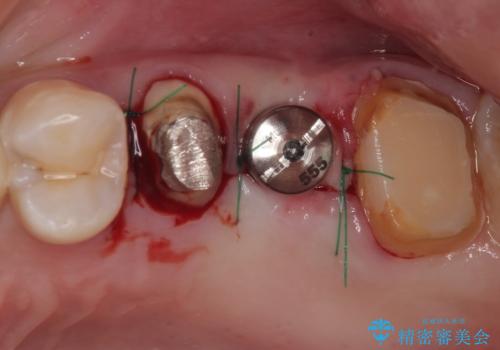

インプラントが必要となった奥歯は、インプラントが埋入できないほど隣の歯の根尖病変が非常に大きかったため、根管治療を行ったうえで半年ほど待ち、骨が再生したことを確認してからインプラントを埋入しました。期間は長くかかりましたが、大変良い仕上がりとなりました。